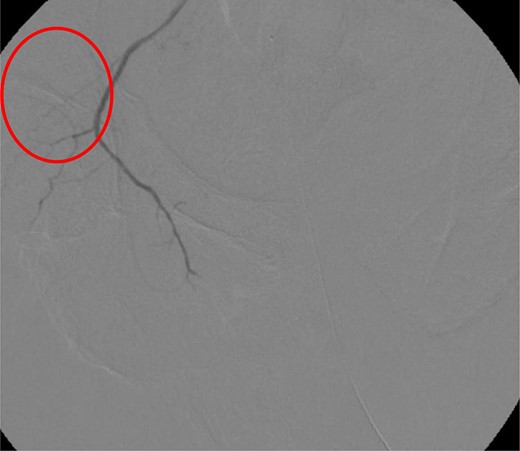

CT abdomen/pelvis with contrast was performed and a blush of contrast was noted posterior to the right pubic bone. Prior to taking patient for exploratory surgery, he was transferred to the interventional radiology suite where a pelvic angiogram was performed revealing an abnormal blush localized to the distal branches of the right iliolumbar artery (Fig. 2). Delayed phase of the angiogram demonstrated early venous filling consistent with a traumatic arteriovenous fistula which was embolized with 300–500 µ of embospheres and three 3 × 2 microcoils (Figs 3 and 4).

CT angiogram demonstrating successful embolization of AV fistula.

After resolution of the traumatic arteriovenous fistula (Fig. 2), a second blush from the right distal internal pudendal artery was identified and successfully treated with Gelfoam slurry. Subsequently, patient underwent exploratory laparotomy which revealed mesenteric and retroperitoneal hematomas. He also underwent craniotomy for evacuation of the subdural hematoma and open reduction internal fixation of the anterior and posterior pelvis. After discharge in fair condition to a subacute rehabilitation facility, patient developed a deep venous thrombosis managed by Coumadin.